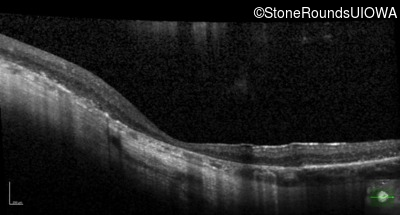

Optical Coherence Tomography - Right - 20/125

Exemplar / OCT Stack